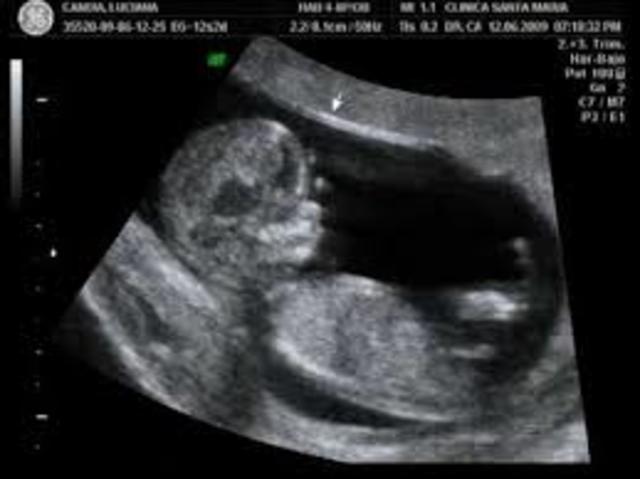

• 12a SEMANA-TERCER MES

12a SEMANA-TERCER MES

El feto mide 9cm. y pesa entre 15 y 20 gramos. La cabeza disminuye su ritmo de crecimiento, para estar más proporcionada respecto al cuerpo. Brazos y piernas se alargan, separándose los dedos de manos y pies. Comienzan a esbozarse las uñas. Aparece el reflejo de succión, será importante para su alimentación en la vida extrauterina. Abre y cierra la boca, lo que hará que trague líquido amniótico, y esto le producirá hipo.

TambIén frunce la frente, patea, extiende los dedos de los pies, cierra las manos y puede girar la cabeza. Todos estos movimientos no son percibidos por la madre, porque el feto es aun pequeño. La placenta, que permite la nutrición del feto por medio de nutrientes que le llegan desde la sangre materna, adquiere forma redonda y en su parte central se inserta el cordón umbilical.